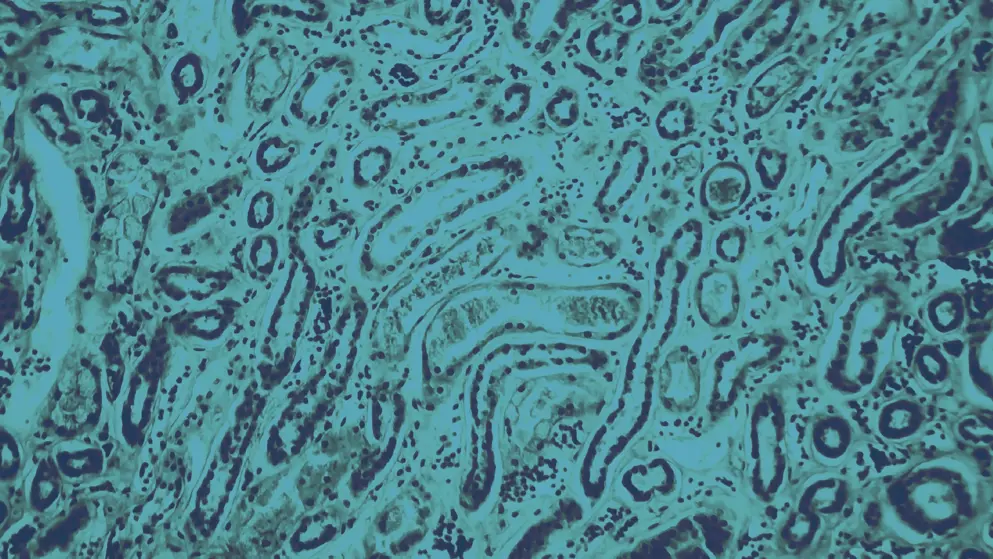

Glomerulonephritis is a subset of renal diseases where immune complexes damage various glomerular structures, such as the basement membrane, mesangium, or capillary endothelium. Such damage to the kidneys can lead to haematuria, proteinuria, azotaemia, and ultimately kidney failure. Timely identification and treatment of specific glomerular diseases, including immunoglobulin A (IgA) nephropathy, focal segmental glomerulosclerosis (FSGS), and lupus nephritis, represents a pressing unmet need. These diseases are clinically challenging to identify, treat, and manage, and approximately 91% of people with FSGS, 81% of people with IgA nephropathy, and 77% of lupus nephritis is not identified or managed properly.

Glomerulonephritis constitutes 25–30% of all end-stage renal disease (ESRD) cases and affects males more than females, with a male-to-female ratio of 2:1. In the early stages of the disease, glomerulonephritis symptoms are often very mild or absent. Without timely identification and treatment, the disease progresses quickly, eventually leading to morbidity within weeks to months, making chronic glomerulonephritis the third most common cause of ESRD. Over the past decade, there has been a significant increase in FSGS, which is positively correlated with the increasing incidence of obesity and the aging population in developed countries. IgA nephropathy remains the most common form of glomerulonephritis globally, with membranous glomerulonephritis more prevalent in Western countries and mesangial proliferative glomerulonephritis more prevalent in many Asian countries.